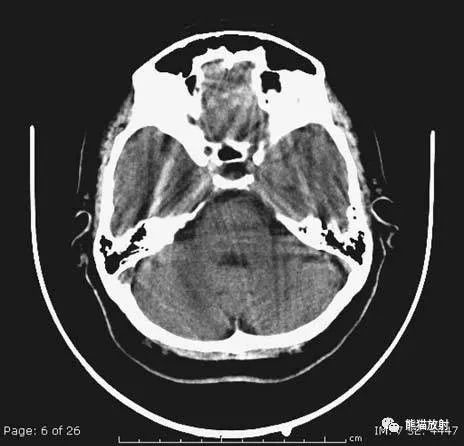

1、颅底层面眦耳线层面

颅前窝底部:眼眶、眼球、筛窦、蝶窦、前床突等。

颅中窝:前界——蝶骨;后界——颞骨岩部(岩骨);内缘——海绵窦及垂体窝;外缘——颞骨,窝内为颞叶,其内侧为海马回。

颅后窝:前缘——岩骨;后缘——枕骨;鞍背后方——脑桥前池,向两侧延伸为脑桥小脑角池。

第四脑室:位于颅后窝中线上,后面紧邻小脑蚓部,其两侧为小脑扁桃体。

延髓、脑桥:位于第四脑室前。